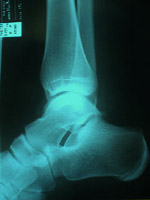

Well - what then happened was the following: We hit a forest track and we go fast downhill. Just before the track finishes I twist over on my right ankle really badly, I carry on running for a minute or two and we get out of the forest. I look down on my ankle and I get a shock! There is a bubble of swelling of the size of a small tennis-ball on the side of my ankle bone. SHIT! I show it to Martin and we both know that the race is over for the both of us.

We struggle for three hours solid to get to the mid way campsite and at the final stretch going downhill from the Scarp Gap Pass my leg has gone completely and Martin is piggy bagging me down all the way pure Vietnam style. We arrive at the campsite and I get some treatment from the first aid team, and eventually we drive off to Keswick Hospital, Penrith Hospital and eventually Carisle Hospital to get an X-ray. Nothing is broken and we head for the pub and look forward to the well known nightlife of Penrith.